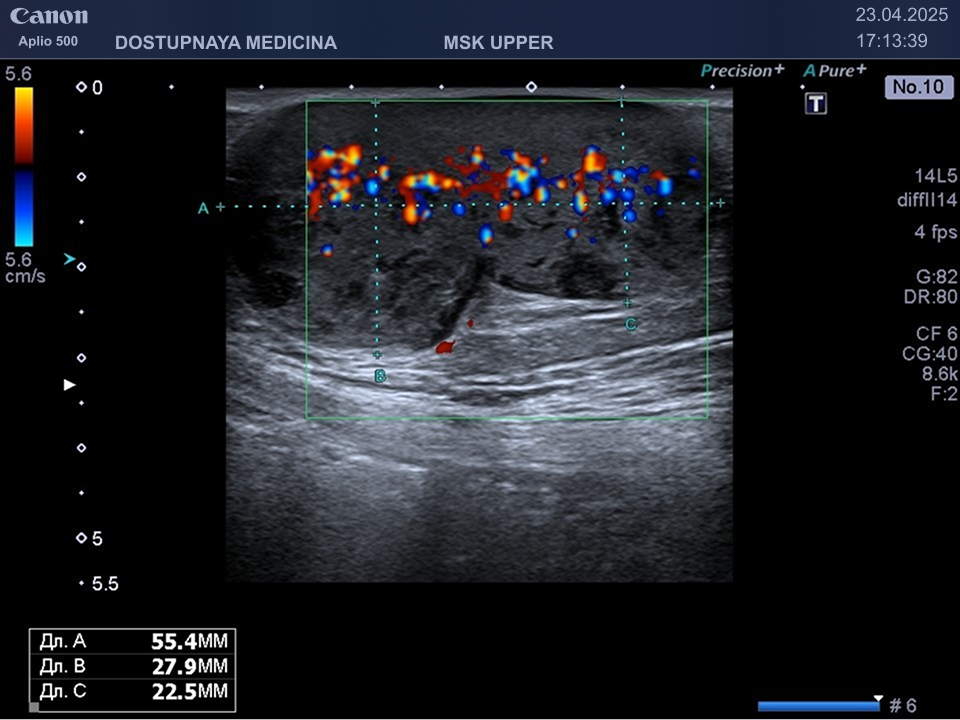

При ультразвуковом исследовании липосаркома чаще всего выглядит, как гипоэхогенное образование неправильной овальной формы, обычно с более пониженной эхогенностью (темнее) по сравнению с окружающей её подкожной жировой клетчаткой, с усиленным кровотоком в режиме ЦДК. В описании заключения важно так же отметить прилежит ли близко опухоль к какому-либо кровеносному сосуду или нерву.

Видно, что кровоток в образовании значительно усилен.